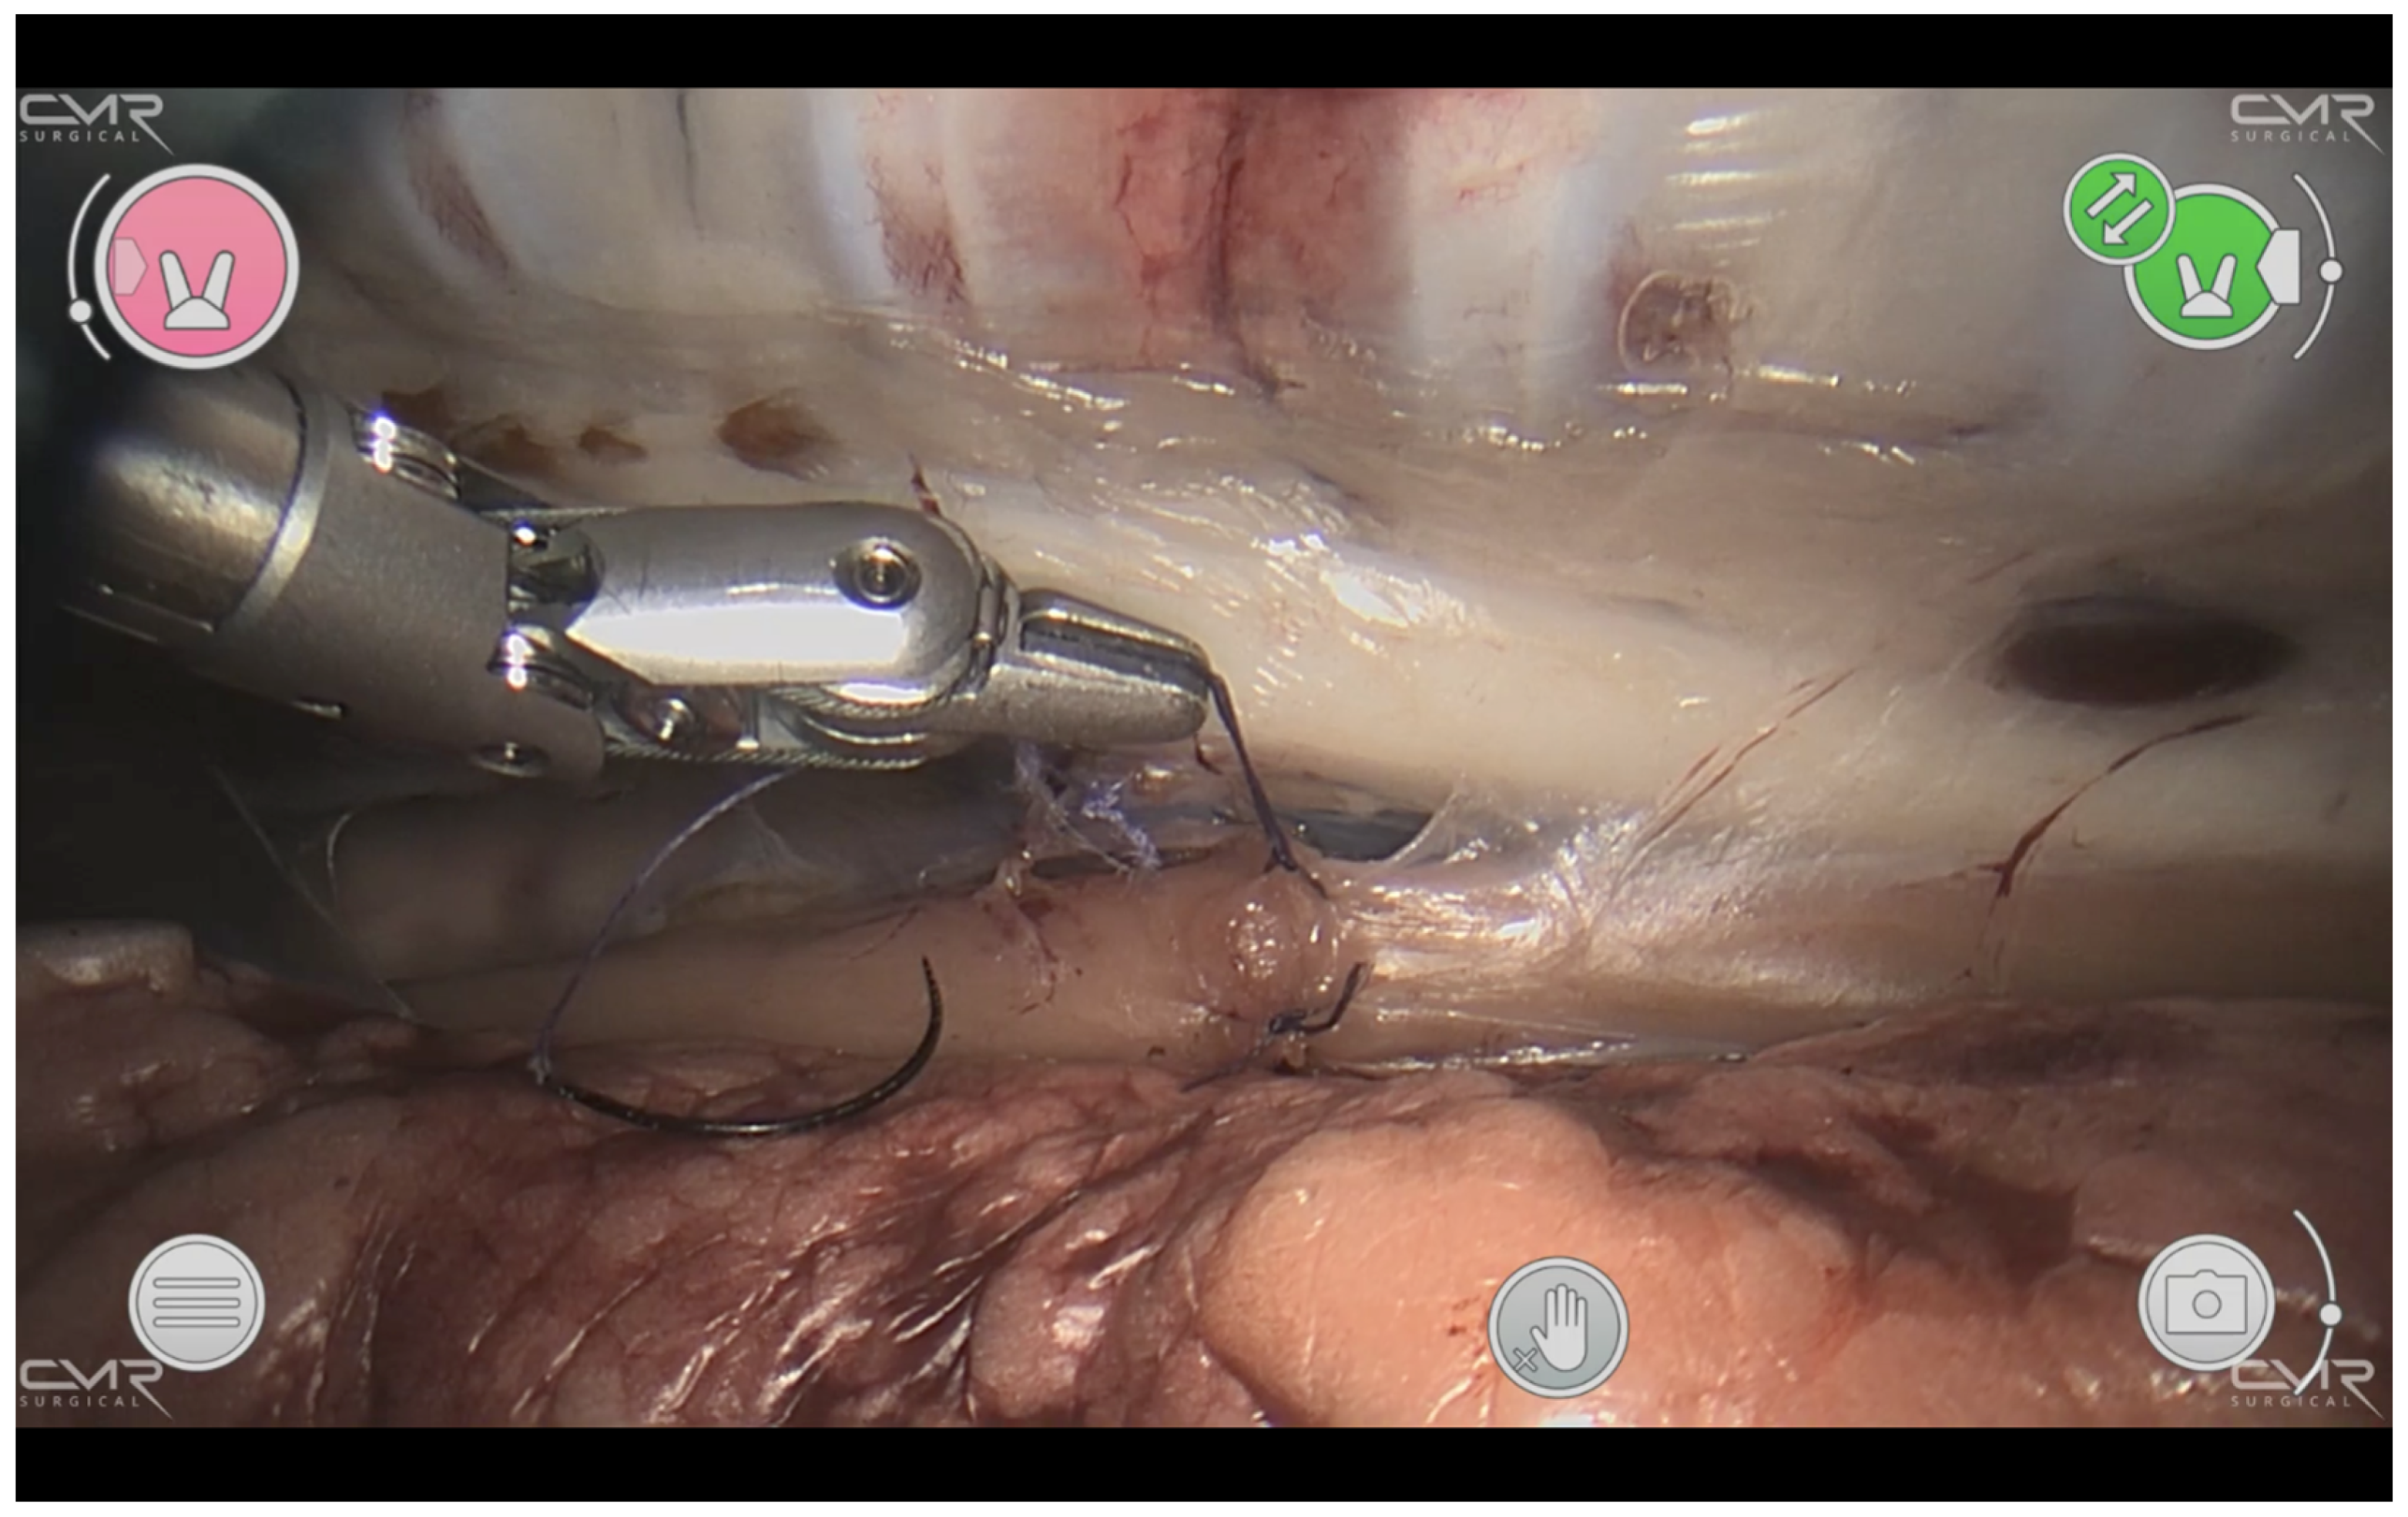

The esophagus was isolated while sparing the vagal nerve. An approximately 8 mm long segment was resected, and the ends anastomosed end to end with interrupted Vicryl 5-0 TF-1 suture (Figure 3).

Figure 3. Thoracoscopic esophageal anastomosis. The esophagus with interrupted stitches can be seen horizontally. A 5-0 Vicryl TF-1 suture is in the surgeon’s left instrument, which has a diameter of 5 mm and demonstrates the confined space that has to be worked in.